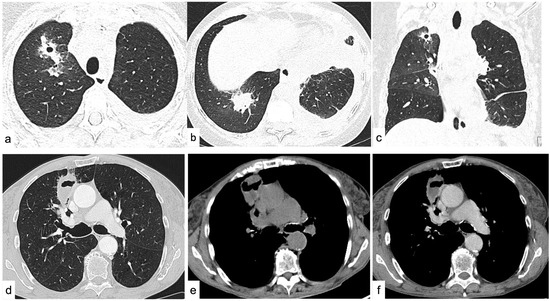

4.1.6. Cavitations and Cysts

4.2. Diffuse Lung Disease

Random Nodules